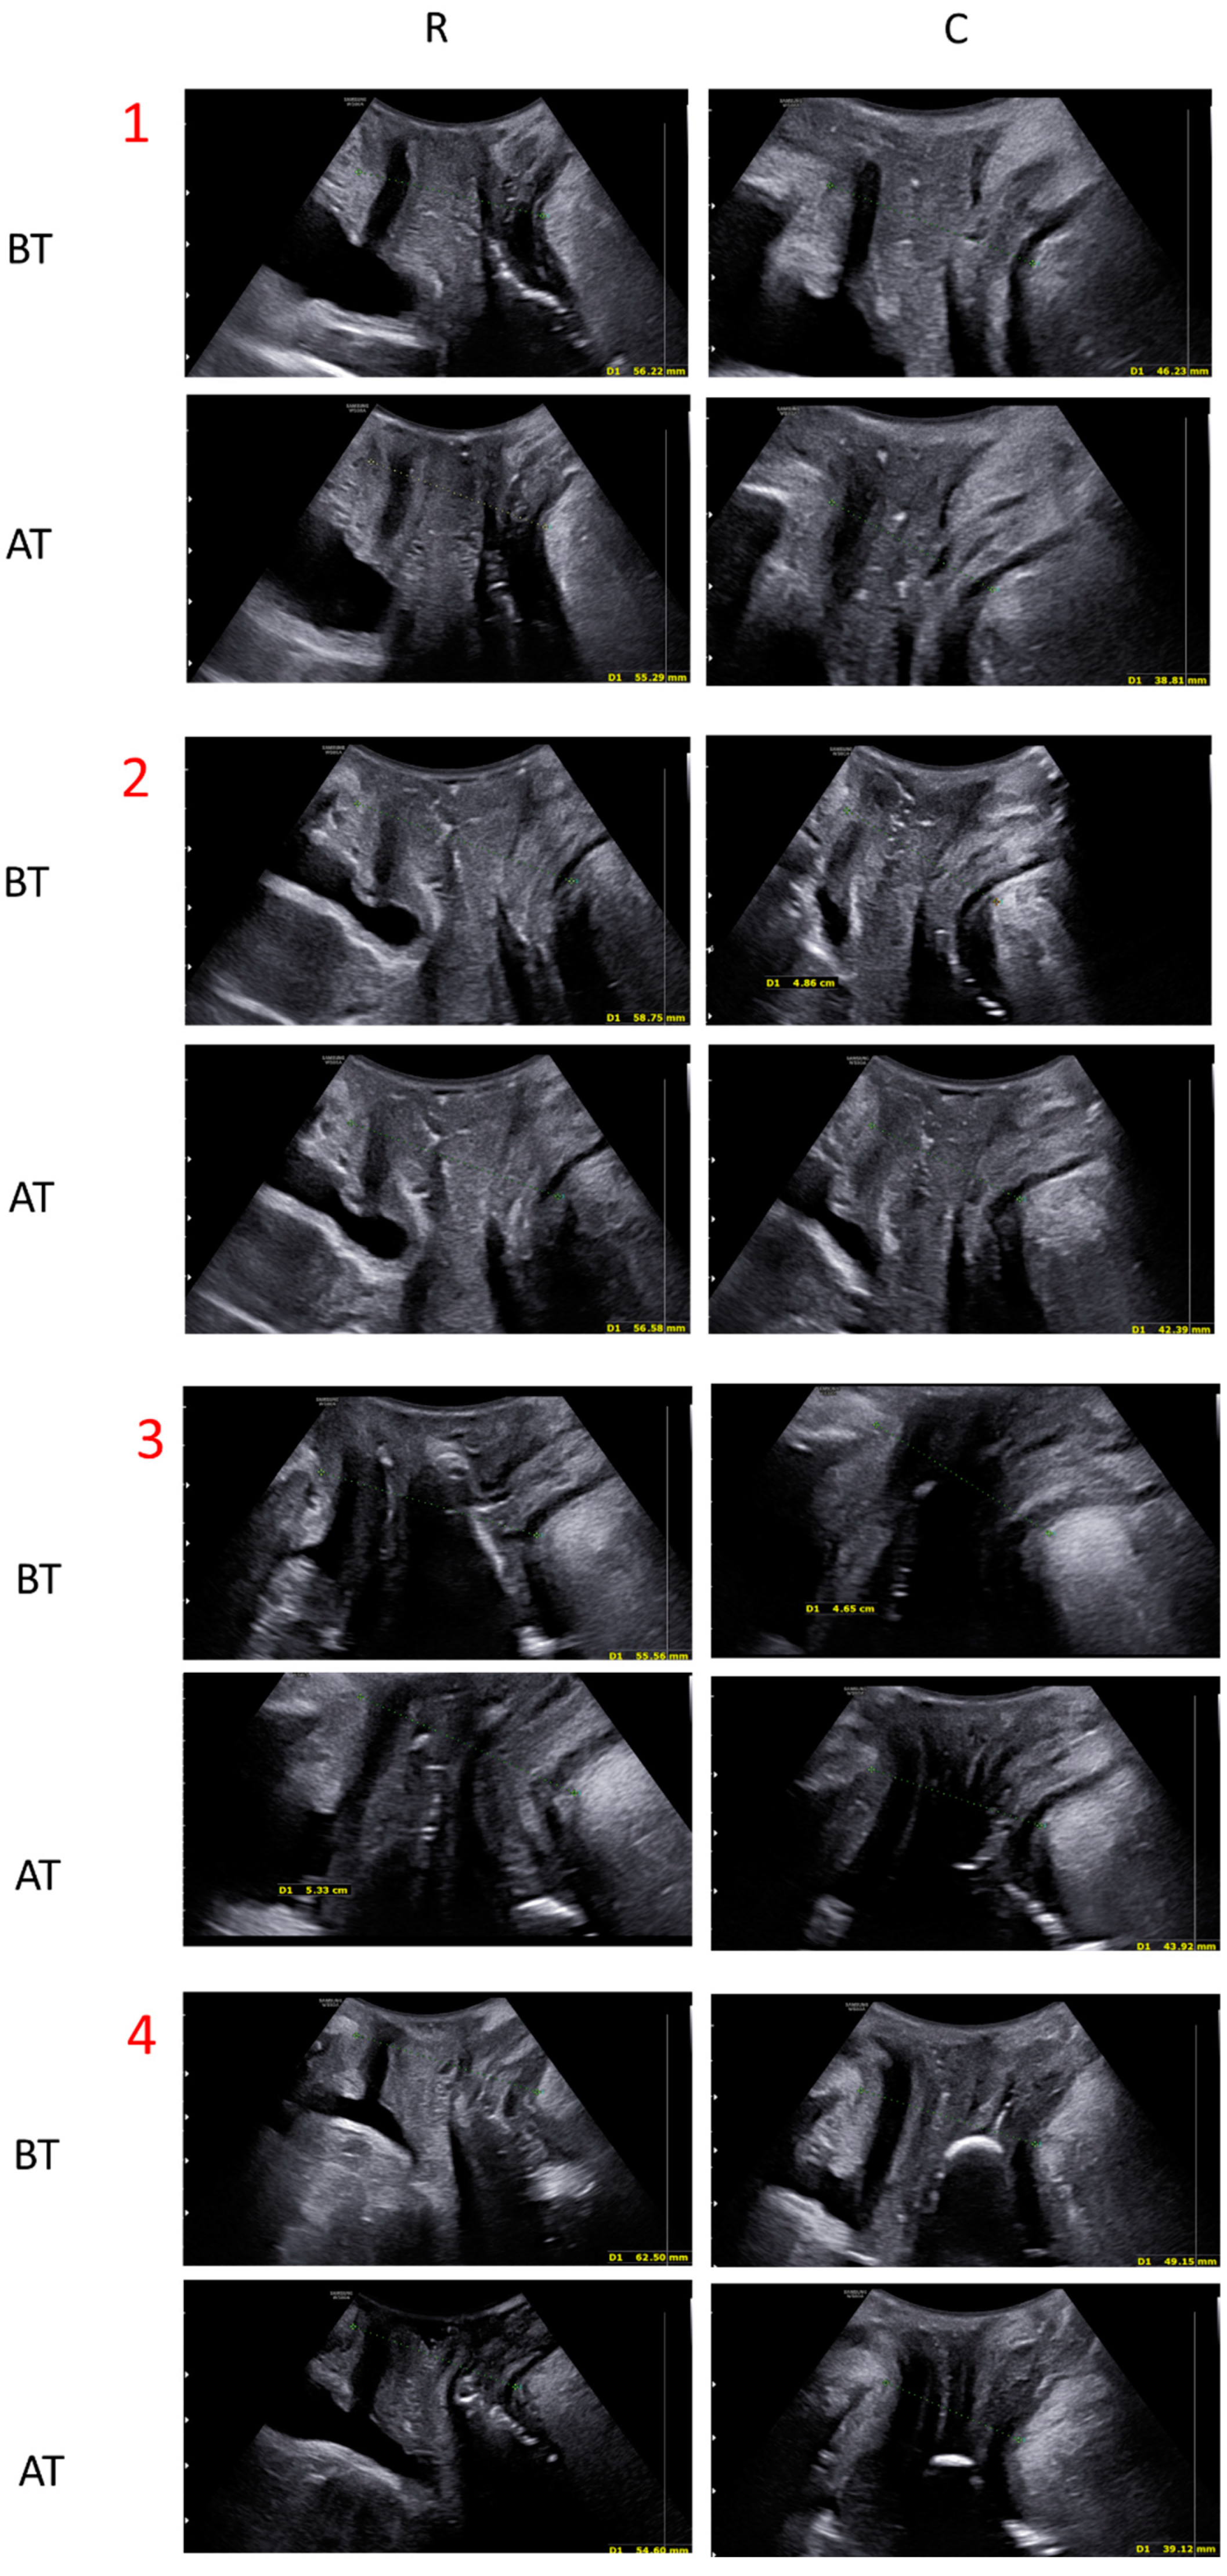

3.1. Quantitative Evaluation: Ultrasound Measurements

| Rest (mm) | Contraction (mm) | |

| Before treatment | 59.74 ± 7.05 | 53.31 ± 8.47 |

| After treatment | 56.37 ± 8.14 | 49.44 ± 8.98 |